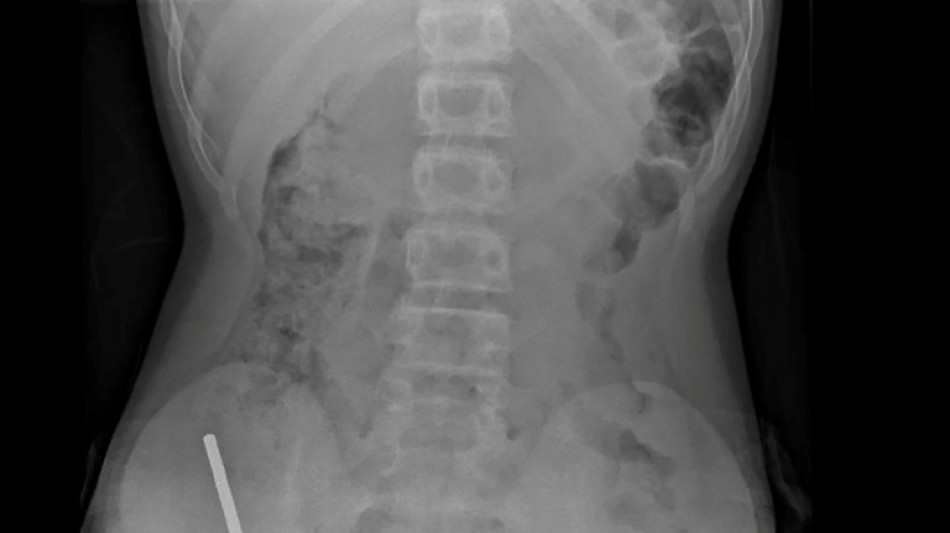

La Quotidienne de Bruxelles - Nouvelle-Zélande: un adolescent opéré après avoir ingéré près de 100 aimants achetés sur Temu